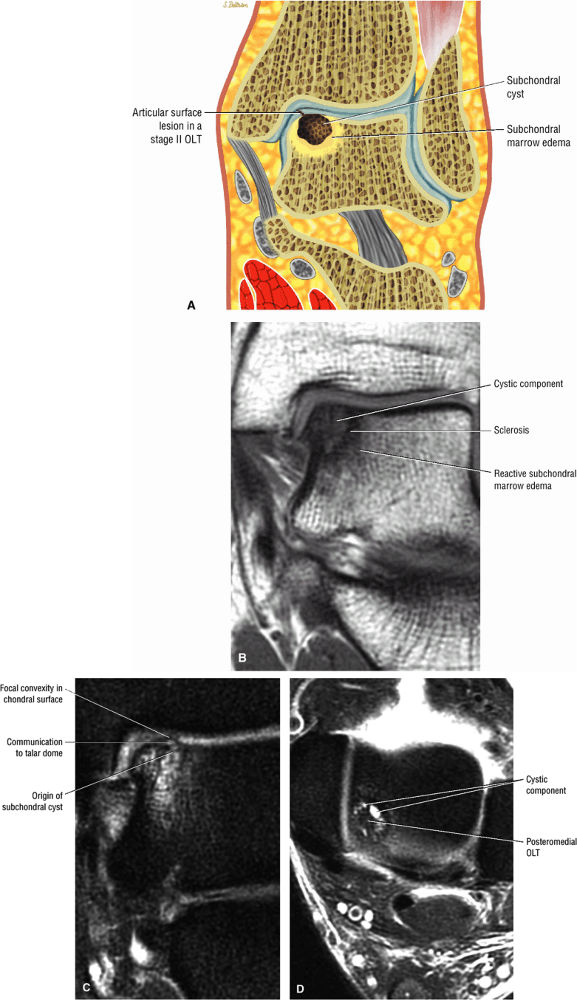

Stage IIA: A subchondral cyst (Fig. 5.96)

FIGURE 5.96 ● Stage II (IIA) OLT of the medial talar dome with formation of a subchondral cyst and anterior communication with an injured chondral surface. (A) Coronal color graphic of medial OLT. (B) Coronal T1-weighted image. (C) Coronal FS PD FSE image. (D) Axial FS PD FSE image.